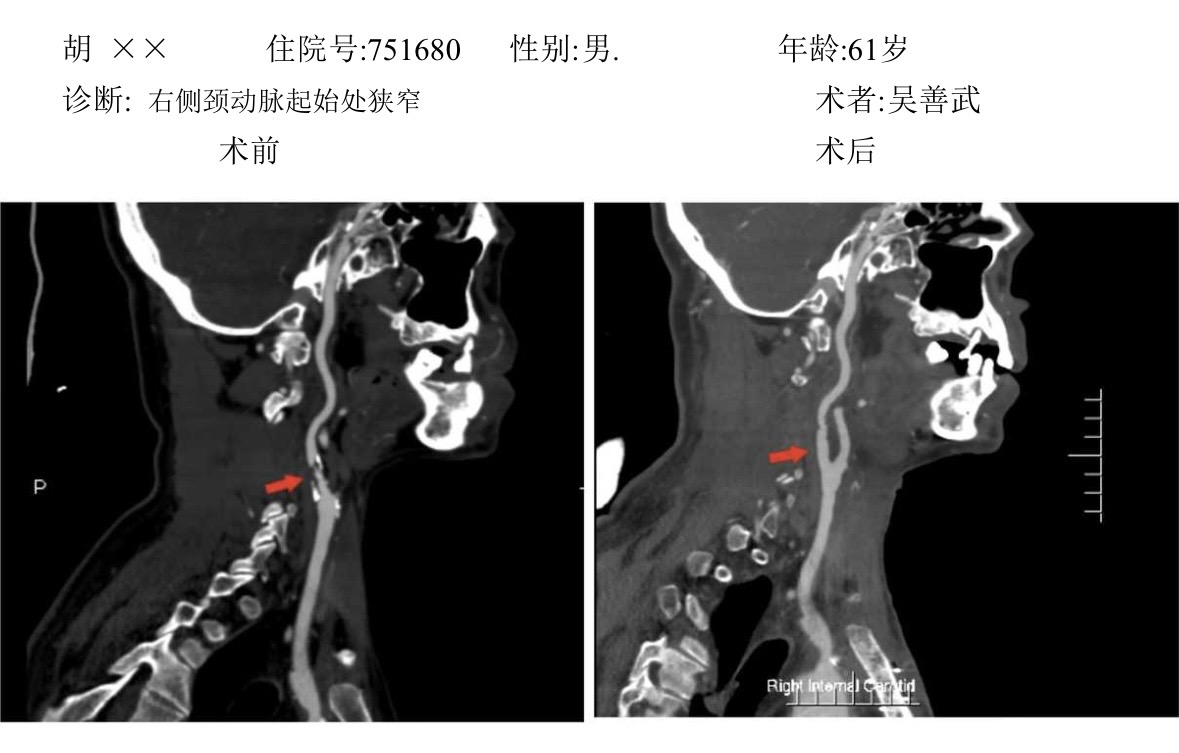

病例分享: 图片4.png图片5.png图片6.png图片7.png